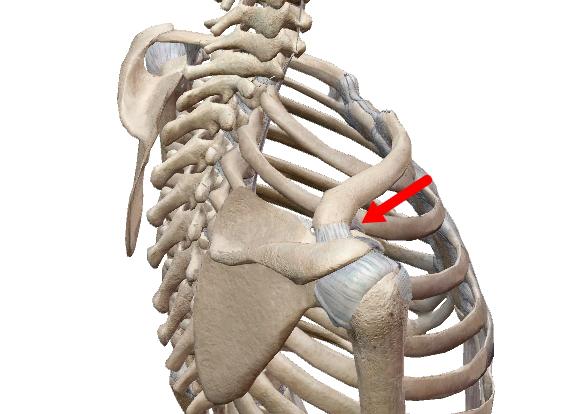

軟骨性関節(軟骨性連結)

硝子軟骨結合と線維軟骨結合の2種がある。

例えば、骨幹と骨端の間にある骨幹板や第一肋骨と胸骨柄を繋ぐ硝子軟骨がそれに当たります。

結合以外に【関節円板】と呼ばれるものは全て(椎間板、半月板、顎関節・胸鎖関節・手関節の関節円盤)は線維性軟骨です。